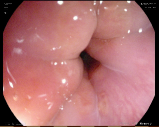

Endoscopies are used to detect diseases in the human digestive system. Images from inside the gastrointestinal tract can help physicians detect diseases early. The used dataset 777https://www.kaggle.com/datasets/abdallahwagih/kvasir-dataset-for-classification-and-segmentation contains eight image categories of the digestive system obtained through the endoscopy imaging technique, as shown in Fig. 8. There are a total of images that can be used in training and testing ML algorithms.